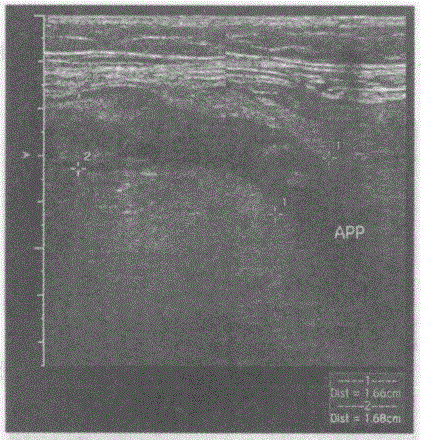

问题 临床资料:女,73岁,自述转移性右下腹痛1天。I 临床物理检查:右下腹麦氏点压痛、反跳痛、肌紧张明显。 化验检查:血常规白细胞12.1×10/L。 超声综合描述:右下腹可见腊肠样低回声区,内回声不均,管腔内径1.61.7cm,与回盲部相连,动态观察内未见蠕动。 {图1} 超声提示:

选项 A.肠套叠 B.肠梗阻 C.急性阑尾炎 D.回盲部实性占位

答案 C